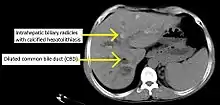

Historically, a cholangiogram would be obtained via endoscopic retrograde cholangiopancreatography (ERCP), which typically reveals "beading" (alternating strictures and dilation) of the bile ducts inside and/or outside the liver. Currently, the preferred option for diagnostic cholangiography, given its noninvasive yet highly accurate nature, is magnetic resonance cholangiopancreatography (MRCP), a magnetic resonance imaging technique. MRCP has unique strengths, including high spatial resolution, and can even be used to visualize the biliary tract of small animal models of PSC.[21]